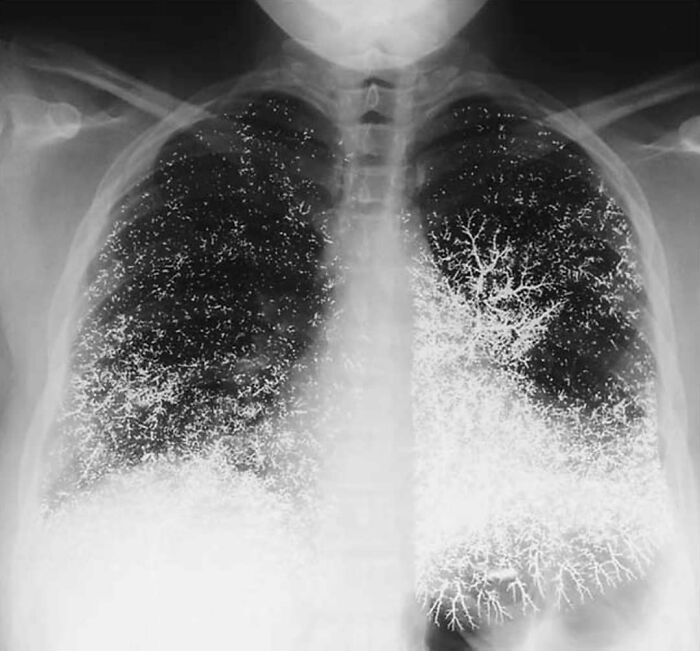

#28 Charcoaled Lungs Of A Heavy Smoker!

Image credits: medicalpedia